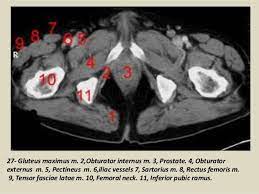

Ct Pelvis Anatomy Muscles - Atlas Of Ct Anatomy Of The Abdomen W Radiology / There are many muscles that form the pelvic floor, including puborectalis, pubococcygeus, iliococcygeus and coccygeus.. The gastrocnemius muscle is a complex muscle that is fundamental for walking and posture. The direct (straight) head and indirect (reflected) head. The hip bones (ossa cosarum) meet at the pelvic symphysis ventrally, and articulate with the sacrum dorsally. These four muscles conjoin to attach to the patella as the quadriceps tendon. We study anatomy at the practical anatomy class we study the human body.

Axial pelvis ct axial femur ct axial femur ct axial knee ct. The muscles of the pelvis, hip and buttock anatomical chart shows how each muscle in this area of the body works with the others, and the various minor systems within the major ones. Hepatocellular carcinoma or liver cancer. The floor is composed of two muscular layers, the levator ani/coccygeus complex and. There are many muscles that form the pelvic floor, including puborectalis, pubococcygeus, iliococcygeus and coccygeus. Pelvic floor muscles that are located wholly within the pelvis. Almost every movement in the body is the outcome of muscle contraction. The muscles are connected with the bones. Learn about anatomy muscles pelvis with free interactive flashcards. The gastrocnemius muscle is a complex muscle that is fundamental for walking and posture. Attached to the bones of the skeletal system are about 700 named. Muscles, connected to bones or internal organs and blood vessels, are in charge for movement. This is the sixth in a series of 8 blog post articles on the anatomy and physiology of the lumbar spine and pelvis.

Ct anatomy of the pelvis. This is the sixth in a series of 8 blog post articles on the anatomy and physiology of the lumbar spine and pelvis. Although ultrasound is frequently indicated for the primary. This article reviews the anatomical and functional information of the gastrocnemius muscle, its embryological derivation. Pelvic girdle and floor female pelvis and reproductive organs male pelvis and reproductive organs urinary bladder and urethra perineum nerves pelvic organ prolapse kegel exercises. To support the abdominal and pelvic viscera. The direct (straight) head and indirect (reflected) head. N patient preparation n patient position n scanogram. Their main function is contractibility. We study anatomy at the practical anatomy class we study the human body. Use the mouse scroll wheel to move the images up and down alternatively use the tiny arrows (>>) on both side of the image to move the images. Abdominal and pelvic anatomy encompasses the anatomy of all structures of the abdominal and pelvic cavities. Hint you are sitting on it right now.

Radiological Anatomy X Ray Ct Mri Kenhub from thumbor.kenhub.com Their main function is contractibility. Axial pelvis ct axial femur ct axial femur ct axial knee ct. Ct anatomy of the pelvis. This mri male pelvis axial cross sectional anatomy tool is absolutely free to use. Rib thorax lumbar pelvis sacrum coccyx femur fibula tibia. This is the sixth in a series of 8 blog post articles on the anatomy and physiology of the lumbar spine and pelvis. The muscles of the pelvis form its floor. Included within the chart are gorgeous illustrations of the pelvic diaphragm, sphincter muscles, gluteus maximus.